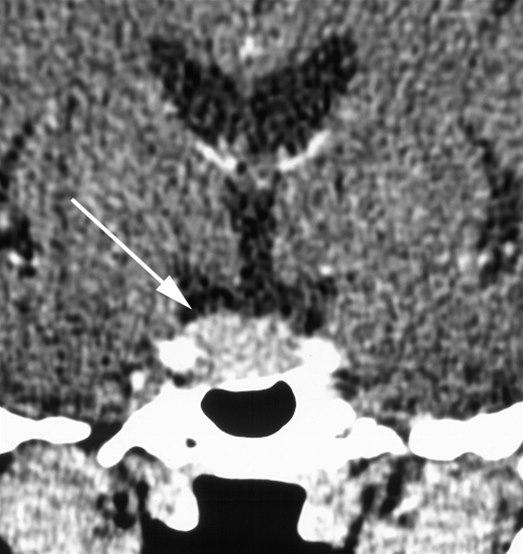

Coronalt snitt gjennom hypofysen etter intravenøs kontrastinjeksjon. Hypofysen (pil) er generelt forstørret, med konvekst bukende konturer.